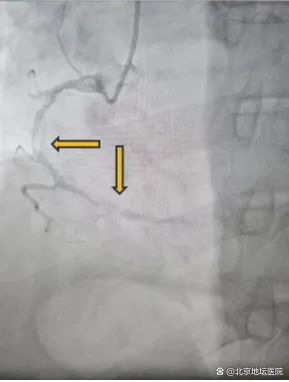

治疗后

“Shockwave冲击波球囊就位,工作压力4atm,释放脉冲!6atm,释放脉冲!”按照预定方案,管浩副主任对病变血管进行治疗,扩张6次后撤出冲击波球囊。复查OCT显示病变预处理充分,随后在右冠脉病变处植入两枚支架,经OCT再次评估支架贴壁良好,冠脉造影示支架展开良好,效果满意。术后,经过医护团队的精心治疗,陈大爷恢复健康,顺利出院。它对管浩副主任医师带领心内科团队的精湛医术和“新武器”——Shockwave冲击波球囊表示认可。